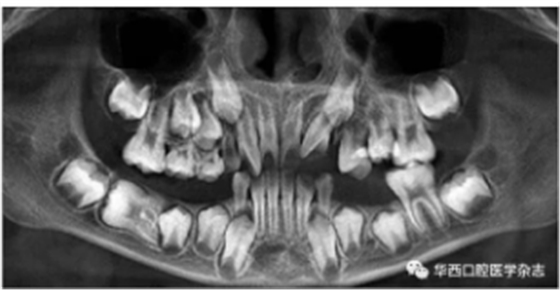

全景片及錐形束CT(cone beam computed tomo-graphy,CBCT)三維重建影像顯示:46牙胚存在,牙冠朝向遠中,且牙長軸與下頜骨下緣接近平行,遠中根發(fā)育約為根長2/3,近中根發(fā)育約為根長1/2且稍向下彎曲,近中根與45牙關系密切,下頜其余牙胚正常(圖2、圖3)。

圖 3 治療前CBCT三維重建